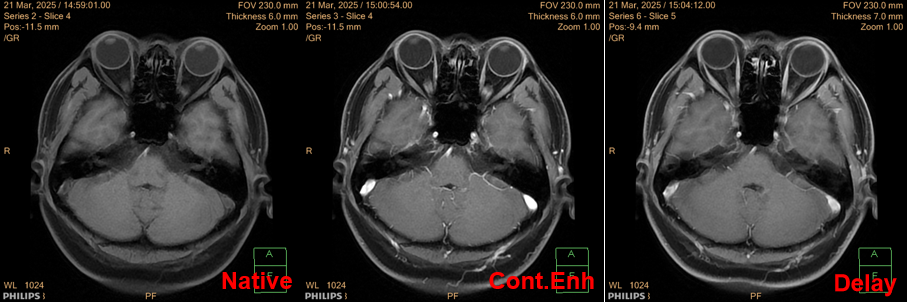

The plain scan report indicates: high signal in the white matter (Fazekas grade I), suspicious low signal in the right cerebellar hemisphere on T2WI with abnormal ADC signal, further examination is recommended; TOF-MRA suggests slight narrowing of the left anterior cerebral artery A1 segment;Therefore, an MRI enhancement scan was additionally ordered; after the examination, no obvious abnormal enhancement was observed, with results as shown in the images:

After completing the examination, the diagnosis and clinical team felt confused about the results; thus, they consulted the author regarding the cause.2. Cause Analysis1.Reasons and Identification of Abnormal Image InformationThe issue was discovered during the plain scan, so we must first look at the images: from the ADC map, we can see significant diffusion restriction in the right cerebellar hemisphere; however, upon reviewing other weighted images, no corresponding abnormalities were found in that area. Where does the description of low signal on T2WI in the report come from? Upon reviewing the report description, I found that “no abnormal high signal was seen in the DWI sequence, and low signal was observed in the right cerebellar hemisphere on b=0 and ADC map with chaotic tubular and patchy low signals”; combined with the actual image performance, we can infer that the report physician’s description of the abnormal T2WI signal was based on the B0 image.As we know, the B0 image of the DWI sequence is equivalent to a T2 star fat-suppressed weighted comparison, which is more sensitive to the Mxy phase acceleration loss caused by B0 field inhomogeneity and is often used to assist in judging fat signals or ferromagnetic substances; ADC reflects the differences in the diffusion coefficients of tissues and supports semi-quantitative measurements; however, it is not directly obtained from the device scanning but is calculated through fitting the signal attenuation of different B values in a single DWI scan; the accuracy and reliability of the ADC value are directly related to the image quality of the DWI sequence: when the original DWI data is affected by other factors, it will inevitably lead to unreliable ADC values.Observing the DWI images, we find that B0 has a low signal, while B1000 has an equal signal, leading to the following interpretations of the image information: ① B0 has a low signal, possible reasons include deposition of ferromagnetic substances, signal suppression of fat components, or the flow void effect of large blood vessels; ② The high B value image has an equal signal, while the B0 image has a low signal, indicating the presence of T2 signal cancellation, and that area is highly restricted in diffusion, while excluding the possibility of flow void effects.Regarding information ①, the possibility of fat components no longer needs to be considered (no corresponding high signal was seen on the T1_FLAIR sequence); as for the flow void effect of large blood vessels, it must be a high signal in TOF-MRA and enhancement scans, and some flow void signals should be observable in conventional T2WI images; however, the interpretation of other sequences does not confirm this; for information ②, T2 cancellation effects are common in vasogenic edema, which inevitably leads to an increase in local water molecule content, yet no signal abnormalities were observed in the corresponding FLAIR sequence, and no abnormal enhancement was seen in the enhancement scan, indicating that the blood-brain barrier in this area was not compromised.Thus, we must consider other possibilities for the abnormality in the original DWI sequence data: if we only interpret the information from the cranial MRI plain scan + MRA + enhancement scan, then there are no obvious abnormalities in the right cerebellar hemisphere; while observing the B value images alone, the information from B1000 matches that of other examinations; if the B0 data has artifacts, it can explain the series of abnormalities and contradictions mentioned above; when B0 has a low signal and B1000 has an equal signal, the calculated ADC will inevitably indicate “restricted diffusion”, but this information is misleading due to B0 artifacts, which can be traced back in the information transmission chain.2. Such cases are not uncommonIn previous posts, I have discussed similar issues: since ADC is calculated from the original DWI data at different B values, when the original data has issues, it will inevitably lead to a decrease in the accuracy of ADC data; in previous posts, the factors causing inaccurate ADC values were due to spatial registration differences, while in this case, the factor causing abnormal ADC values was B0 image artifacts.